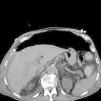

Varón de 78 años ingresado en cuidados intensivos por hematoma subdural con desarrollo de síndrome de distrés respiratorio agudo (SDRA) por neumonía nosocomial y desconexión prolongada de la ventilación mecánica invasiva. Traqueostomizado y precisando gastrostomía percutánea (PG) se inicia ventilación mecánica no invasiva (VMNI) como apoyo en retirada de respirador, desarrollando neumoperitoneo en radiografía de control (fig. 1) de manera asintomática, descartándose perforación de víscera hueca o complicaciones de la PG mediante prueba de imagen con contraste oral (figs. 2 y 3). La VMNI es causa muy infrecuente de neumoperitoneo benigno a tener en cuenta en pacientes ventilados y portadores de gastrostomía. El tratamiento debe ser conservador.